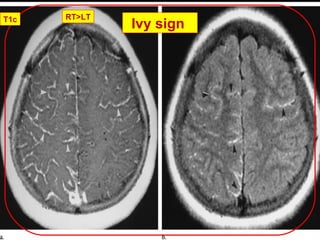

2. Ivy sign: Marked diffuse leptomeningeal

enhancement on postcontrast T1-weighted and FLAIR

images. Considered to represent the fine vascular

network over the pial surface.

 vivid contrast enhancement and high signal on FLAIR due

to slow flow.

(a) Transverse postcontrast T1-

weightedMR image shows

diffuse leptomeningeal

enhancement, with some

enhancement of perforating

arteries (arrowheads) in basal

ganglia. Areas supplied by the

posterior cerebral artery are

relatively spared.

b) Transverse unenhanced

FLAIR MR image shows subtle

high signal intensities

(arrowheads) along

leptomeninges in bilateral

frontal regions and was

interpreted as equivocal.

Ivy sign

T1c

FLAIR

RT>LT

Ivy signT1c